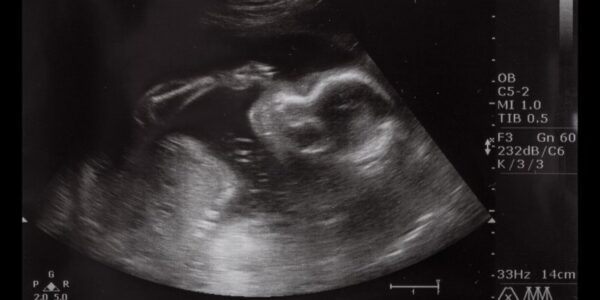

Jak przebiegają kroczki badania prenatalnego?

Przygotowanie do badania Kiedy dostajesz informację, że spodziewasz się dziecka, wizyta u lekarza staje się nieodzowna. Badanie prenatalne jest kluczowym elementem opieki nad ciążą. Przygotowując się do tego ważnego kroku, warto dowiedzieć się, jakie badania będą przeprowadzane i jak będą…